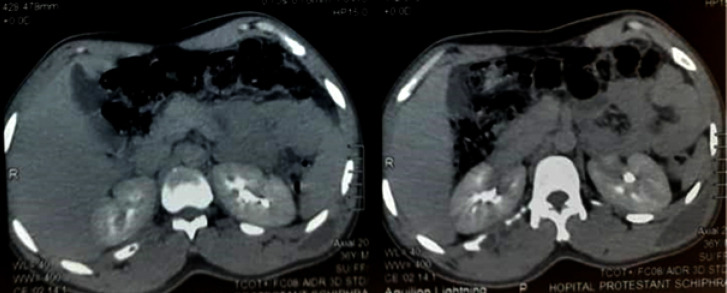

Observation: A 36-year-old black African patient of Burkinabè origin, with a history of tuberculosis infection (his mother had pulmonary tuberculosis) and no other pathological history, presented with chronic inflammatory cervicalgia that had been developing for six months in a non-febrile context of altered general condition. Examination showed a left latero-cervical swelling associated with a left basithoracic swelling, both fluctuant. Pleuropulmonary and neurological examinations were normal. HIV serology and tuberculin skin test were negative. Cervico-thoracic computed tomography revealed multiple abscesses. The abscesses were incised and drained. Analysis of the specimen showed the presence of acid-fast bacilli by direct examination and Mycobacterium tuberculosis by Xpert test, with sensitivity to rifampicine. The diagnosis was multiple tuberculous cold abscesses associated with cervical Pott's sore. The patient was started on standard analgesics and antituberculosis drugs for 12 months. The course was favorable, with a follow-up of one year after treatment.